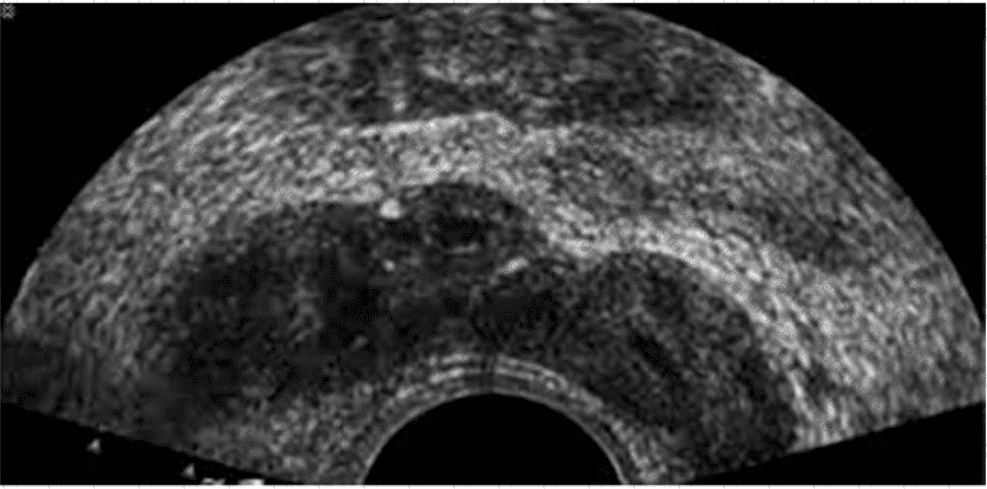

The ultrasound image shown is a transverse endorectal (transrectal) ultrasound, commonly used to evaluate the prostate and adjacent structures. The two hypoechoic (dark) oval-shaped structures seen superior and posterior to the prostate are characteristic of the seminal vesicles.

The seminal vesicles are paired, elongated glands located superior and posterior to the base of the prostate and are best visualized in transverse planes on endorectal imaging. They appear as hypoechoic or anechoic structures with internal septations, depending on the degree of fluid content.

This image most clearly demonstrates the bilateral seminal vesicles.